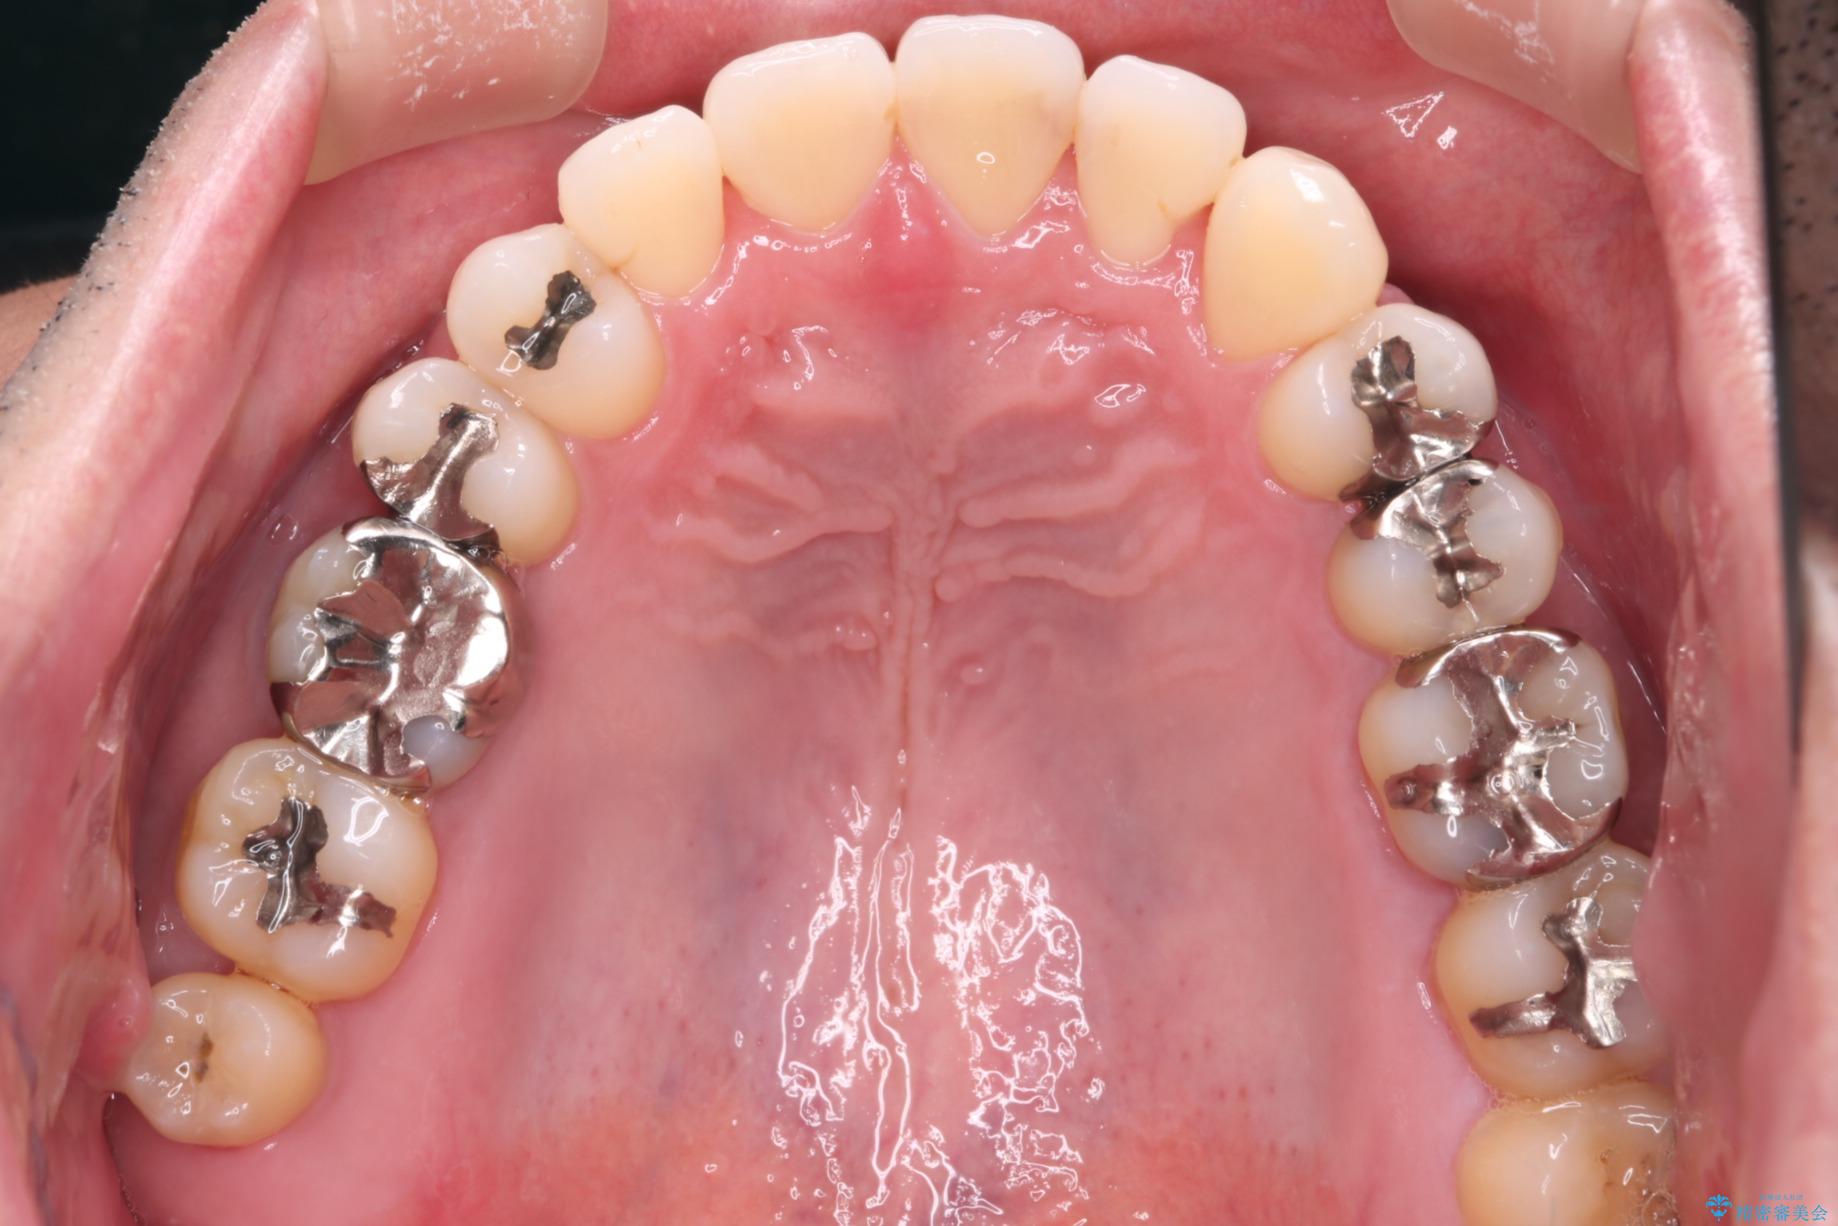

【メタル装置】1本のみ抜歯してワイヤー矯正

- 右上2番目の歯が舌側転位していることと前歯の叢生(がたつき)を主訴に来院されました。

右上の犬歯が初診時よりかなり歯根露出しており、矯正の力をかけるとさらに歯根露出するリスクがあるため、右上の2番目の歯を前に出すためにも

右上の犬歯を抜歯して歯並びを整える治療計画を立てました。

下のがたつきをとるために、IPR(歯と歯の間を削る処置)も行って歯を並べていきます。